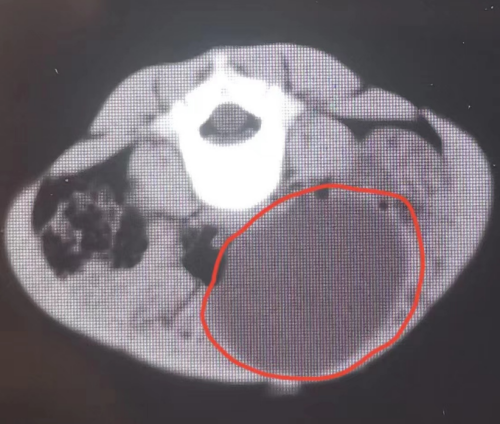

入院后,超声科副主任医师钟卓敏为雯雯仔细复查了腹部彩超,提示其左卵巢上长了一个直径约8cm的肿瘤。通常来说,卵巢肿瘤发病年龄越小,恶性肿瘤的可能性越大,而且雯雯半年前超声下肠套叠复位时还没有发现肿瘤,半年内长到了8cm,更应警惕卵巢恶性肿瘤可能。

妇产科副主任魏馨针对雯雯的病情,详细解答了家属的各种疑虑。4月10日,在麻醉科、手术室和儿科的通力协助下,手术团队为雯雯精心地设计了手术方案,妇产科副主任魏馨主刀,麻醉科主任刘松华负责麻醉。经过多学科紧密配合,医生完整取出肿瘤,后病理报告为良性畸胎瘤。得知肿瘤为良性,不用切除卵巢,保留了孩子的生殖功能和内分泌功能,雯雯的父母喜极而泣,不断地对医护人员表示感谢。